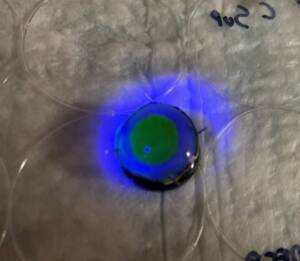

Photos of the Petri plates, 72 hours after bacterial (Streptococcus canis) inoculation.

The image and the inset show complete (positive) bacterial growth inhibition (full translucency)

at the treatment site after one dose of UV-C for 15 seconds at a 10 mm distance.

The blue lines divide the plate into quadrants.